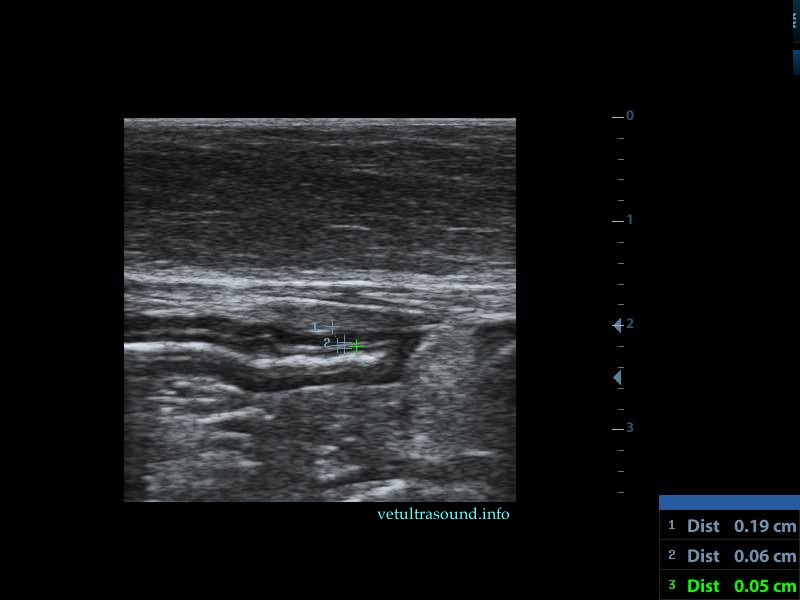

Findings: There was an increase in thickness of a segment of the small intestine, in which the normal layering was lost. This lesion extended for 3 cm(pic1). There was a restriction of the lumen, in this segment(pic2). In other parts of the ileum the muscularis propria was increased in thickness, compared to the thickness of the submucosa and the mucosa(pic3,4). The renal cortex of both kidneys was hyperechoic compared to the echogenesity of the liver and the spleen(pic5). A small amount of ascites was noted. The regional lymphnodes were enlarged and the mesenteric fat, which encircled the lesion of the small intestine, was hyperechoic.

Diagnose: These findings are compatible with alimentary tract lymphoma. There is a possibility that the kidneys are also infiltrated by lymphocytes.

pic5